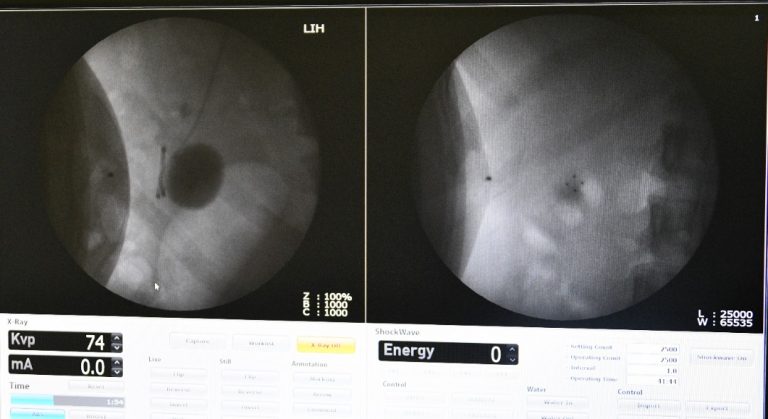

Hospitali ya Taifa Muhimbili-Mloganzila imeanza kutoa huduma ya matibabu ya kuvunja mawe kwenye figo na mfumo wa mkojo kwa njia ya mawimbi mshituko kwa kitaalam Extracorporeal shock wave lithotripsy (ESWL).

Huduma hii inafanywa kwa kutumia mashine ambayo inatoa mawimbi sauti yanayosafiri kupitia ngozi hadi kwenye figo sehemu yenye jiwe au mawe. Mawimbi hayo hugeuka kuwa nishati yenye uwezo wa kuvunja mawe kuwa madogo mithili ya mchanga ambapo yakishasagwa yanatoka kwa njia ya haja ndigo (kukojoa).

Kwa upande wake Daktari Bingwa wa Upasuaji wa Mfumo wa Mkojo MNH-Mloganzila Dkt. Hamis Isaka ametaja faida ya matibabu haya, kuwa hayahitaji mgonjwa kulazwa hospitalini kwani anaweza kutibiwa na kuruhusiwa kwenda nyumbani siku hiyo hiyo ili kuendelea na shughuli za ujenzi wa taifa.

"Faida ya upasuaji huu ni kuwa mgonjwa anaweza kufanyiwa siku hiyo hiyo na kuruhusiwa kuendelea na shughuli zake za kila siku pia uwepo wa huduma hii unaondoa ulazima wa upasuaji mkubwa kwa wagonjwa hawa" amesema Dkt. Isaka.